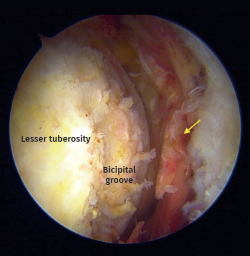

Radiological assessment included preoperative magnetic resonance imaging (MRI) of the affected shoulder, reviewed independently by the operating surgeon. MRI was used to confirm the diagnosis (Figure 1), classify the tear according to Lafosse classification, assess tendon retraction, fatty infiltration (Goutallier classification) on the sagittal plane, rule out advanced degenerative changes, and evaluate associated biceps pathology (Figure 1).

Figure 1. Axial magnetic resonance image of full-thickness acute subscapularis tear. Arrow: Torn subscapularis tendon.